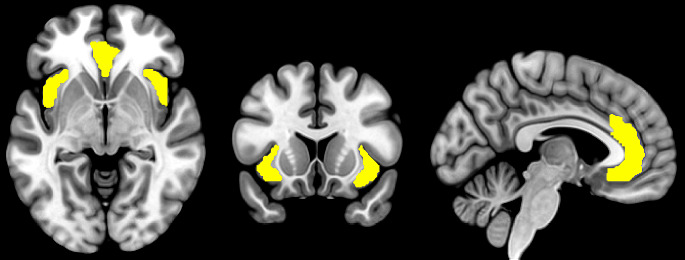

Purpose of review: The brain's salience network (SN), primarily comprising the anterior insula and anterior cingulate cortex, plays a key role in detecting salient stimuli and processing physical and socioemotional pain (e.g., social rejection). Mounting evidence underscores an altered SN in the etiology and maintenance of substance use disorders (SUDs). This paper aims to synthesize recent functional neuroimaging research emphasizing the SN's involvement in SUDs and physical/socioemotional pain and explore the therapeutic prospects of targeting the SN for SUD treatment.

Abstract Image